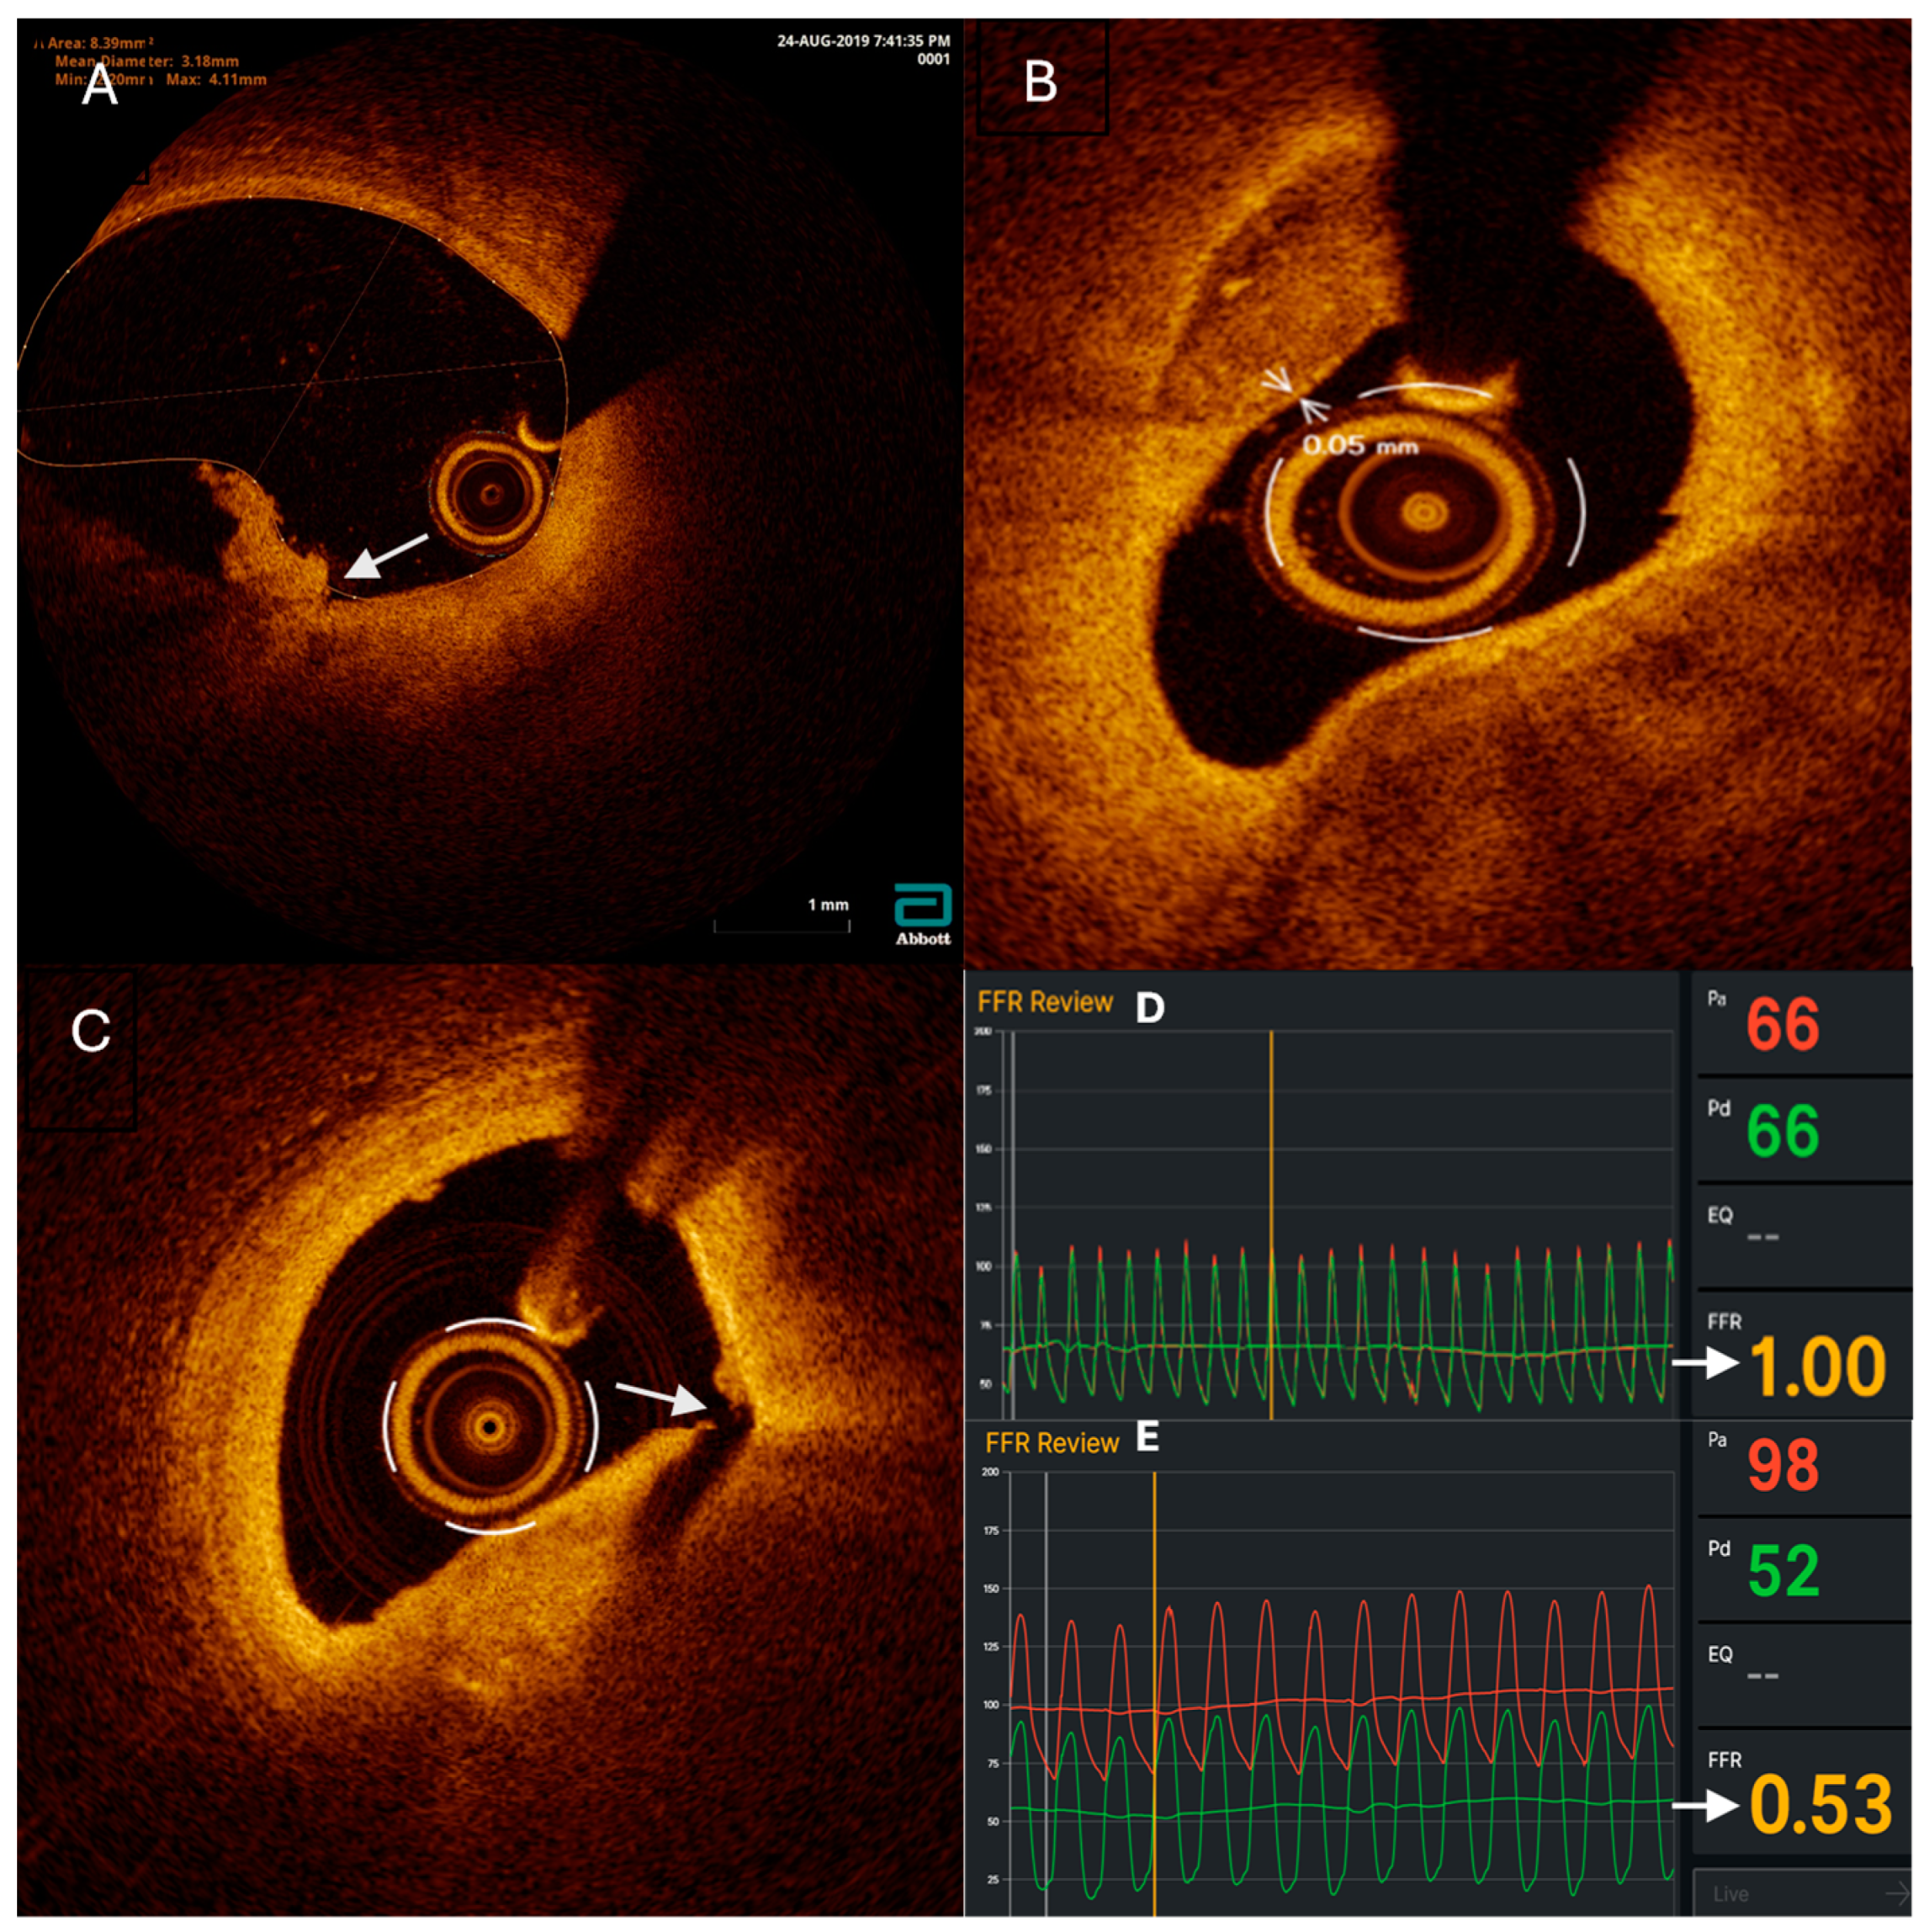

| FFR values | |

| RCA, mean ± SD | 0.88 ± 0.07 |

| ADA, mean ± SD | 0.85 ± 0.04 |

| ACX, mean ± SD | 0.89 ± 0.08 |